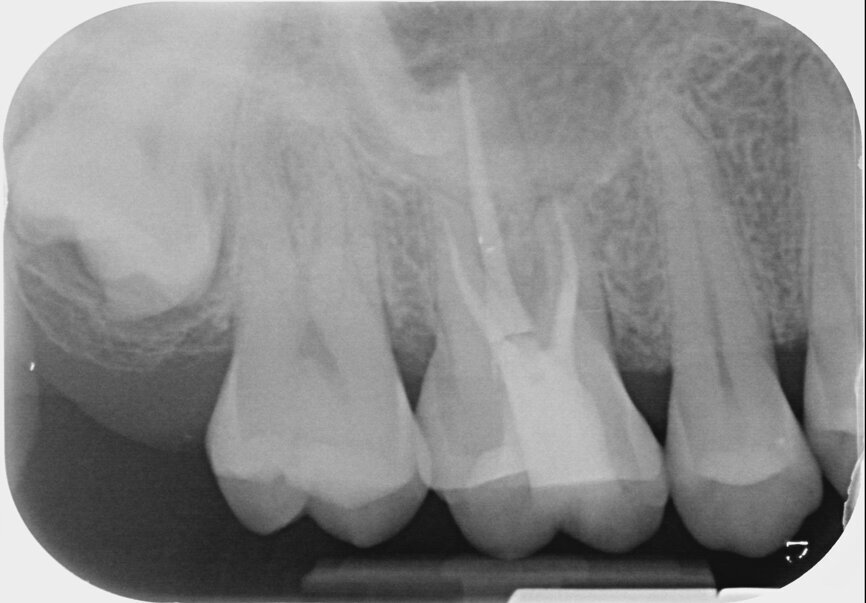

She had been stressed and grinding. More deliberation, still no further was the diagnosis. The tooth was dressed once again, with a change in the medicament. Still no joy. A restorative dentist then proceeded to drill the crack out and restore with composite. Still no joy. The tooth was taken out of occlusion when one dentist noticed the development of periodontal ligament widening on one of the long-cone periapical radiographs. The root canal treatment was completed jointly by two excellent endodontists and the second mesiobuccal canal was located. Under any other circumstances, it was a fantastic clinical outcome. Unfortunately, the pain was unabating (Fig. 2). Let us see as much as we can. A CBCT scan was taken that was also inconclusive (Fig. 3). Was it something to do with the sinus? The radiographic report was suggestive, but again nothing conclusive. Towards the end of the two weeks, the patient marched herself into the office of the exodontist to have the tooth extracted. Misery. We had failed.